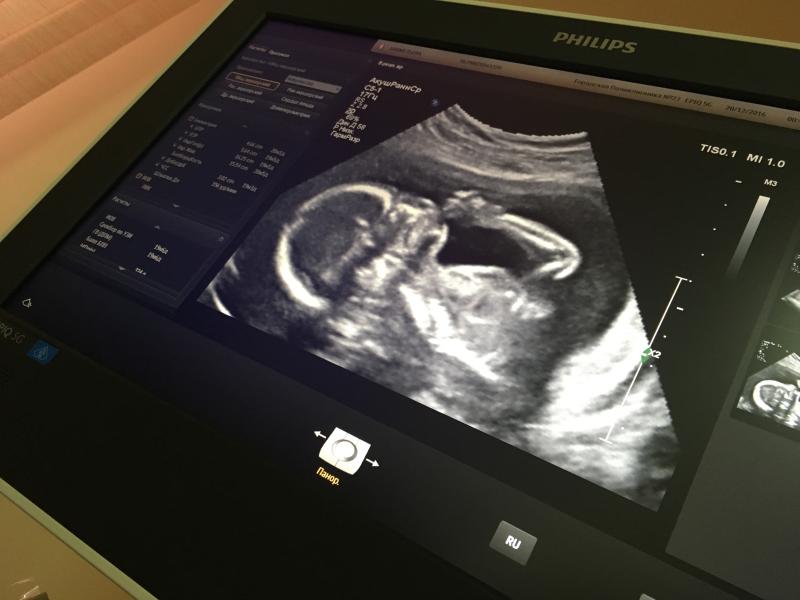

У нас сегодня был второй скрининг

И моему счастью нет предела💗💗💗

Мы ждём маленькую принцессу🍼👸🏽

Спит с пальчиком во рту☺ моя сладенькая